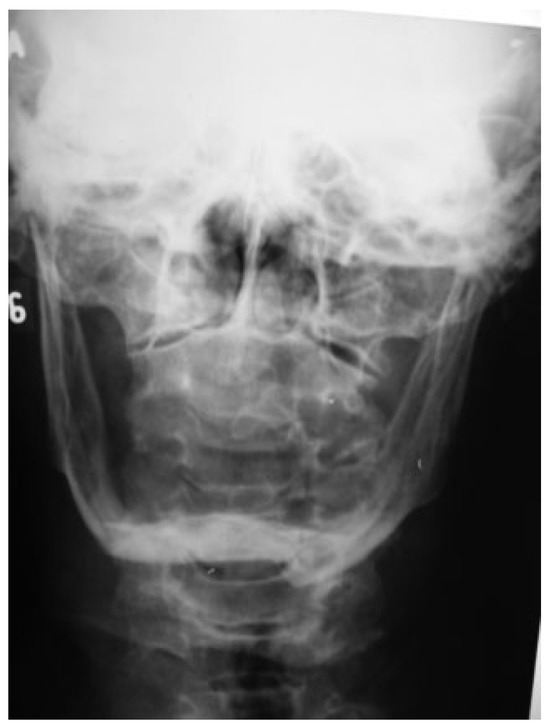

An 81-year-old woman was referred to the University Hospital after a fall. An oral exam and mandibular X-rays (Figure 7 and Figure 8) revealed two fractures of the mandibular bodies, one on each side. The patient presented mouth-opening limitation and bilateral lower-lip paresthesia. According to Luhr et al. [12] classification, the patient presented a class III atrophic mandible and its height at the lowest point was 5 mm.

Figure 7. Preoperative posteroanterior mandibular radiograph.